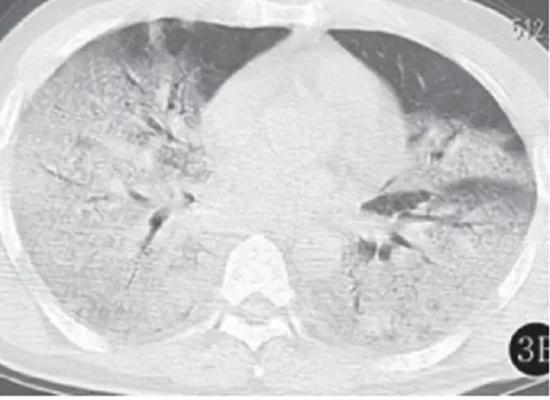

若病毒大量復制,或者患者免疫功能較弱時,會發展為危重癥。此時病毒會攻擊多個肺葉,肺泡損傷彌漫,病變范圍擴大、融合,造成雙肺實變,即從CT上看,患者的肺部呈一大片的白色狀,醫學上稱之為“白肺”。這種情況會嚴重影響肺換氣,患者需要持續吸氧。

▲白肺(圖片來自網絡)

按照國家衛健委發布的新型冠狀病毒肺炎試行第六版診療方案之中的臨床分型,新冠肺炎分為輕型、普通型、重型及危重型。在患者的肺部CT中,輕型者沒有比較明顯的肺炎改變;普通型者以肺部出現局限性斑片狀或很多節段性片狀“病灶”為主(圖②);重型者雙肺可出現較多的白色小斑片“病灶”,部分融合成大片狀“病灶”(圖③);危重型者會有“白肺”表現(圖④)。

▲從上到下依次為普通型、重型及危重型新冠肺炎患者的肺部CT表現(圖片來自網絡)